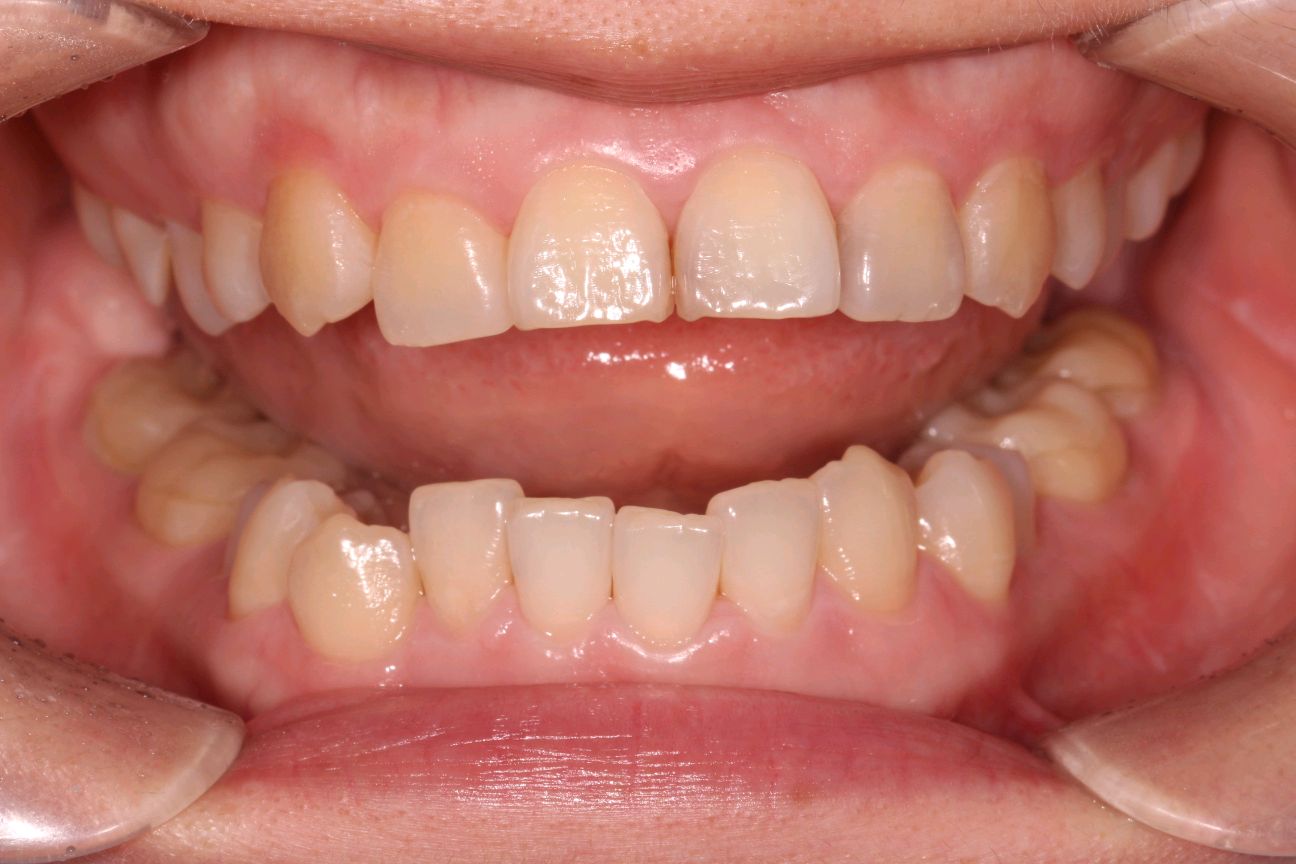

客户诉牙齿进食冷热酸痛敏感,检查发现各牙邻接面龋坏,告知患者各种备选修复材料的优缺点、相应修复费用和修复时间、可能的复诊次数和并发症,患者选择了嵌体修复。

0.1%的聚维酮碘溶液局部消毒,涂表麻膏,4%盐酸阿替卡因肾上腺素注射液0.8ml局部浸润麻醉,等待麻药生效后。去净腐质,基牙预备基牙预备,排龈,精修,CEREC扫描,比色,CEREC制作嵌体,试戴后边缘密合,符合各种对修复体的质量和设计要求,患者满意,同意粘固。消毒基牙和修复体,酸蚀冲洗,隔湿,吹干,粘接做永久固定,调合抛光,交代注意事项,常规医嘱,按时复诊,客户表示一次就诊方便快捷,很满意。